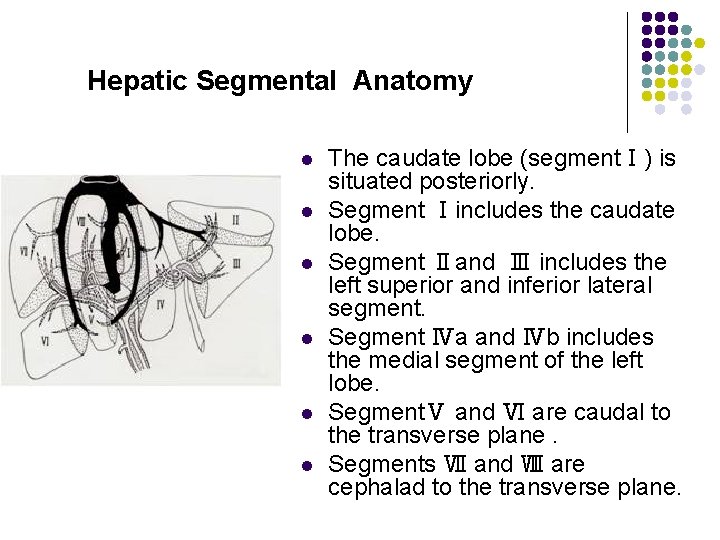

Hepatic Segmental Anatomy l l l The caudate lobe (segmentⅠ) is situated posteriorly. Segment Ⅰincludes the caudate lobe. Segment Ⅱand Ⅲ includes the left superior and inferior lateral segment. Segment Ⅳa and Ⅳb includes the medial segment of the left lobe. SegmentⅤ and Ⅵ are caudal to the transverse plane. Segments Ⅶ and Ⅷ are cephalad to the transverse plane.